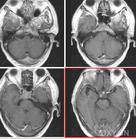

CT表現:

①腫瘤最常見於松果體區,位於鞍上區腫塊常累及漏斗。

②CT平掃多呈等密度或稍高密度腫塊,無出血、壞死及囊性變,可分葉,但境界清楚;瘤體本身鈣化少見,典型松果體區生殖細胞瘤常見腫瘤包埋松果體鈣化灶。

③增強掃描呈中等至明顯的均勻強化。

④室管膜下轉移可表現為沿腦室壁線狀或條片狀強化,沿腦脊液向蛛網膜下腔播散表現為腦表面、腦池的線狀或結節狀強化。